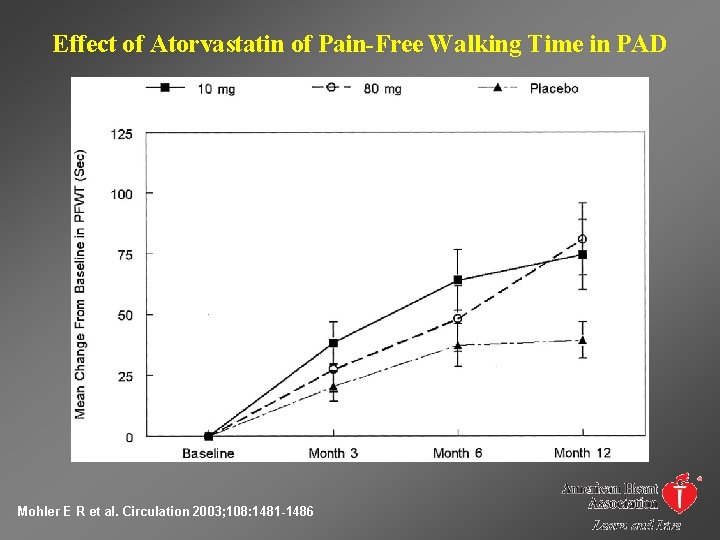

Effect of Atorvastatin of Pain-Free Walking Time in PAD Mohler E R et al. Circulation 2003; 108: 1481 -1486